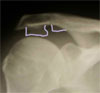

Zwapnienie w przyczepie mieśnia nadgrzebieniowego (m.supraspinatus) na zdjęciu rentgenowskim

(biała plamka nad głowa kości ramiennej).

Na tym zdjeciu widoczne są wielkie zmiany wyrostka barkowego ze zwapnieniem w regionie przyczepu więzadła kruczo-barkowego i zmiany obojczyka w regionie stawu barkowo-obojczykowego.

Zmiany radiologiczne w stawie barkowo-obojczykowym.